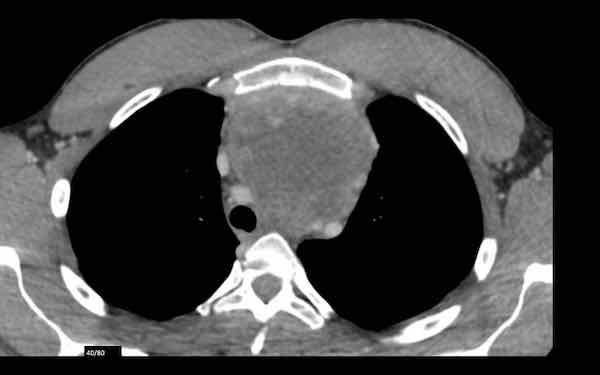

Đây là hình ảnh của một nam giới 24 tuổi.

Hãy quan sát kỹ các hình ảnh trước.

Câu hỏi: đây có phải là tuyến ức bình thường không?

Hình ảnh

Mặc dù tuyến ức này khá lớn, nhưng có hình tam giác bình thường và chứa mỡ (mũi tên).

Đây là tuyến ức bình thường.